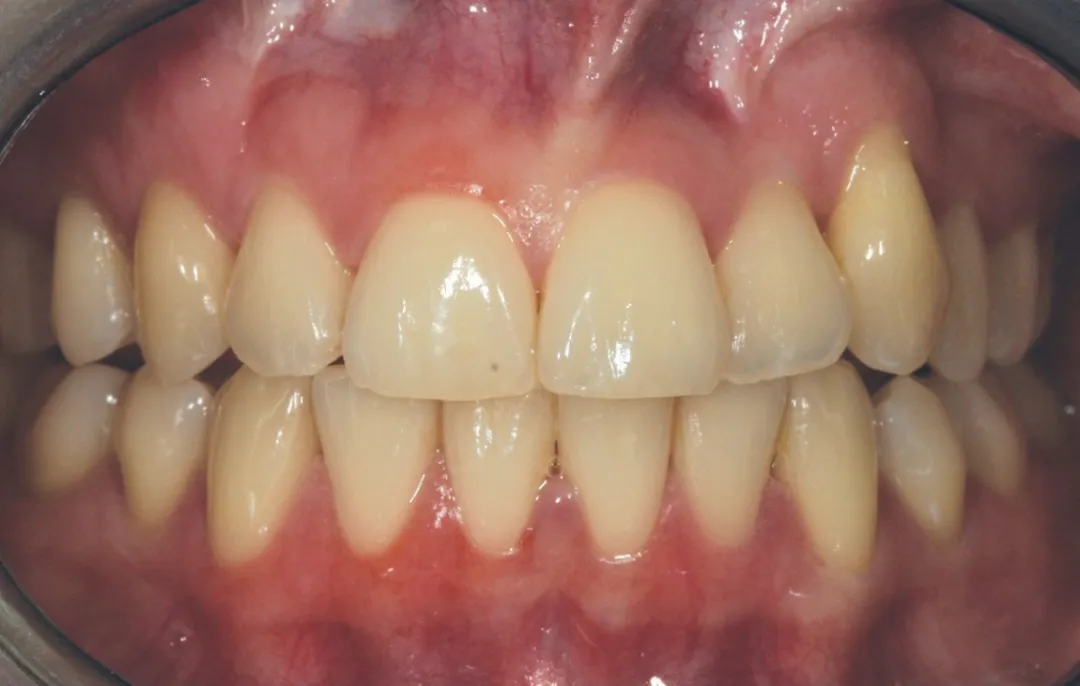

2 号病例 - Patrick EXBRAYAT 医生(图 21 至 35)

22 岁患者,23 异位,行正颌外科种植术后 22 出现严重根吸收。

图 21 :术前临床检查。

图 33 :最终完成,自然微笑。

图 34 :挤压安装最终修复体。